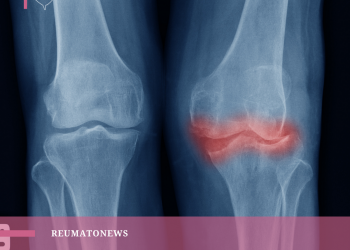

Osteoartrite > Artrose